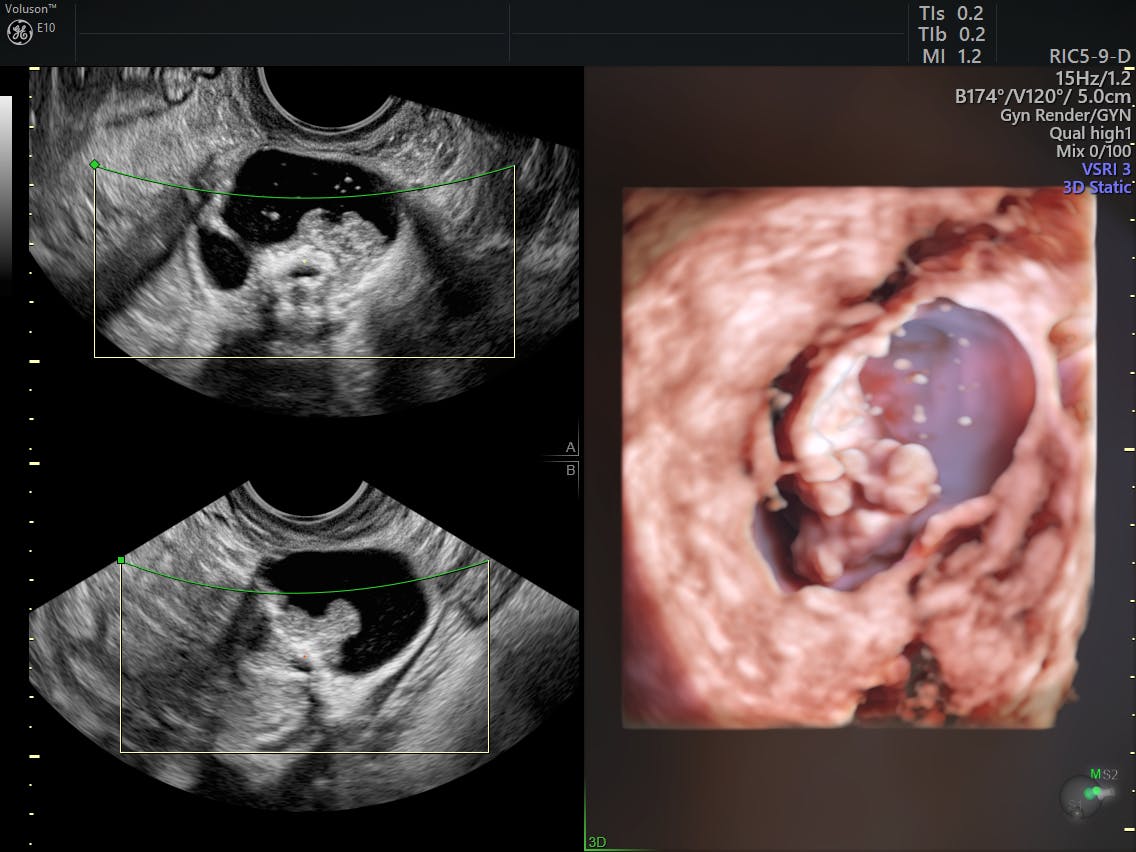

What 3d Ultrasound Can Tell You About Ovarian Cancer Empowered